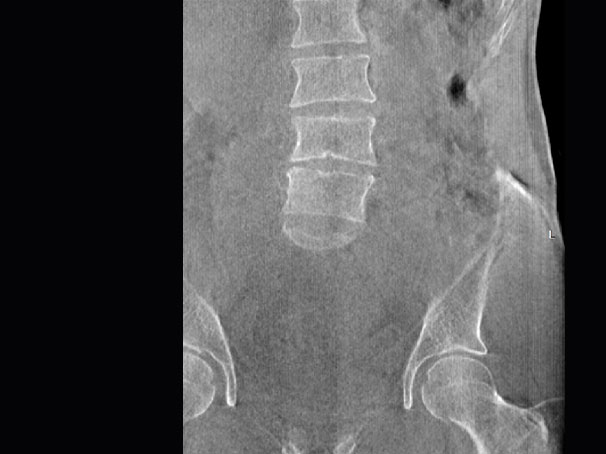

• 全身姿态评估

WR-3D能提供一种负重位状态下全身的姿态和三维空间任一平面平衡评估,使全脊柱术后评价更客观、真实 。通过各种临床参数包括骨盆、脊柱参数评价骨盆、脊柱平衡,避免由于髋膝屈曲造成的代偿性脊柱失衡的发生,WR-3D提供了三维空间任一平面平衡评估测量方法,可以更加定量地评估手术效果 。